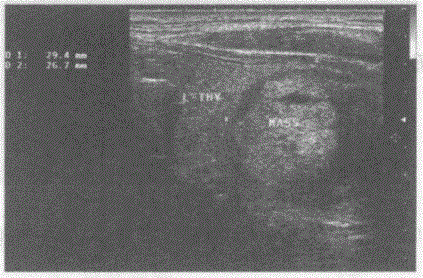

问题 临床资料:女,41岁,自述无意中发现颈部肿物半年。 临床物理检查:左侧颈部可扪及肿物,边界清晰,可随吞咽上下移动。 超声综合描述:甲状腺左叶增大,中部可见2.9cm×2.6cm圆形不均质回声区,边界清晰,有完整包膜,内回声由无一低一中等回声,CDFI:内血流信号不丰富。 超声提示:

选项 A.甲状腺癌(左叶) B.甲状腺腺瘤并囊性变(左叶) C.甲状腺囊肿(左叶) D.甲状腺炎性结节(左叶)

答案 B